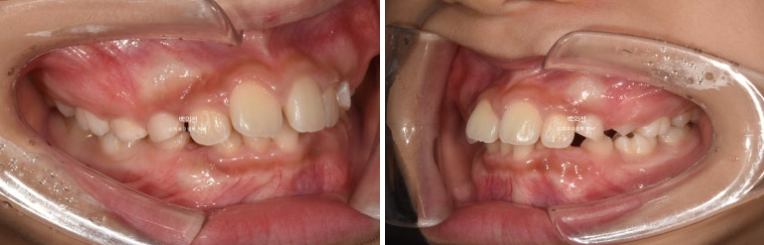

과개교합은 개선이 되어 아래앞니가 보이고 중심선은 잘 맞습니다.

앞니 뻗침과 돌출은 해결이 되었고 그 사이 남아있던 유치가 여러개 빠졌습니다.

좁았던 악궁이 넓어지면서 모양이 잡혔고

24.02

삐뚤했던 아래 앞니는 가지런해졌고 송곳니는 악궁확장을 통해 공간이 생기면서 제자리로 잘 올라오게 되었습니다.